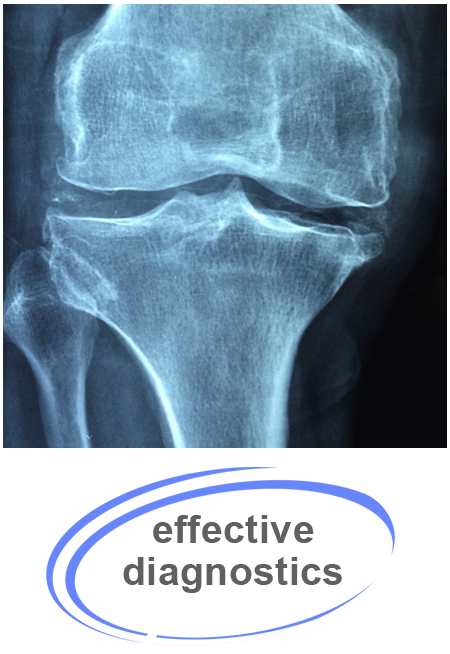

Because chiropractic care uses spinal manipulation and other techniques that involve movement of skeletal components with the hands or with the use of the instrument, an X-ray can show a chiropractor exactly what is happening in the body in terms of alignment and structure.

It is important to highlight that X-rays are not used universally in chiropractic care. In most patients, the chiropractor is able to determine what is occurring in the musculoskeletal system without the need for imaging technology. X-rays are usually reserved for the more severe cases in which there may be a serious condition present such as scoliosis, osteoporosis, or spinal stenosis.

As a general guideline, X-rays are recommended in the following cases:

• If the patient has sustained a significant traumatic injury, as a bone may be broken or a joint may be dislocated

• If an infection may be causing the patient's pain

• If any significant disease is suspected, such as cancer or a possible tumor

• If any type of joint disease is suspected, such as arthritis causing joint pain

• If the patient is over age 50 and has experienced any type of trauma (even a minor one)

• For most patients over 65 years of age

• Anyone who has been diagnosed with or who may be at risk for osteoporosis.

• The X-ray may be important to identify or rule out a possible vertebral fracture from osteoporosis.

• tendonitis

• Any suspected spinal instability

• If the patient has had long-standing pain that has not responded to or resolved with previous health care treatment